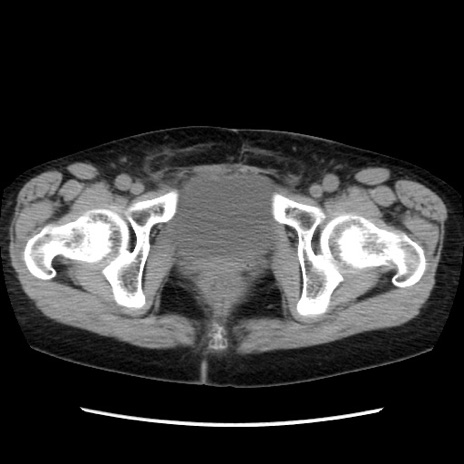

症例32(横断像)

【症例】40歳代 女性

【主訴】上腹部痛、嘔気・嘔吐

【現病歴】約9時間前頃から急に上腹部痛、嘔気、嘔吐が出現。改善しないため救急要請。

【既往歴】子宮頚癌(広汎子宮全摘術、放射線療法)、腸閉塞

【身体所見】腹部:平坦、軟、腸雑音亢進、上腹部を中心に腹部全体に圧痛あり。

【データ】WBC 8400、CRP 0.03